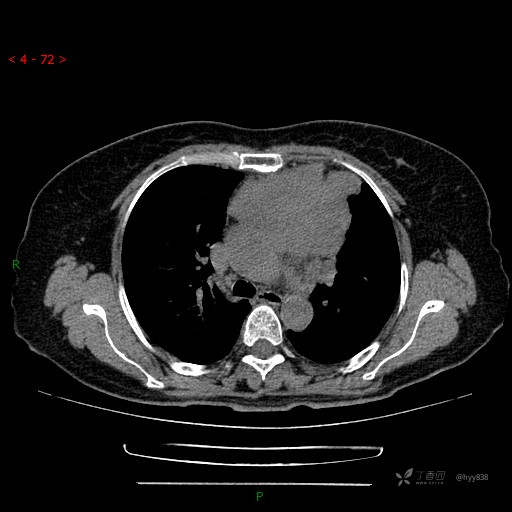

简要病史:患者诉3月余前患新冠肺炎,出现持续性胸闷,活动后可缓解,无胸前区压榨感,无畏寒发热不适,无胸痛咯血、呼吸困难,无恶心、呕吐,无腹痛、腹胀、腹泻等不适,未予以重视,未行特殊处理。患者胸闷持续存在,为进一步诊治,3天前于本院查胸部CT提示前纵膈团块状软组织密度影,肿瘤性病变可能,心包积液,左上肺磨玻璃结节,右下肺增殖灶可能建议进一步检查。门诊以“前纵膈占位” 收入我科。 患者本次起病来精神、食欲、睡眠尚可,大小便正常,体力、体重无明显变化。

辅助检查:CT

临床诊断:纵隔占位

胸部CT平扫